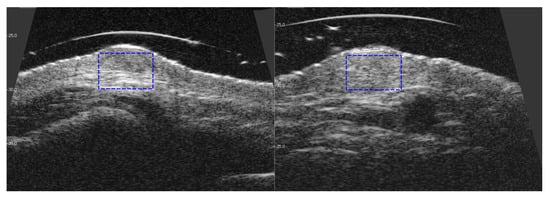

3.3. Visible and Ultrasound Changes in Scar Area